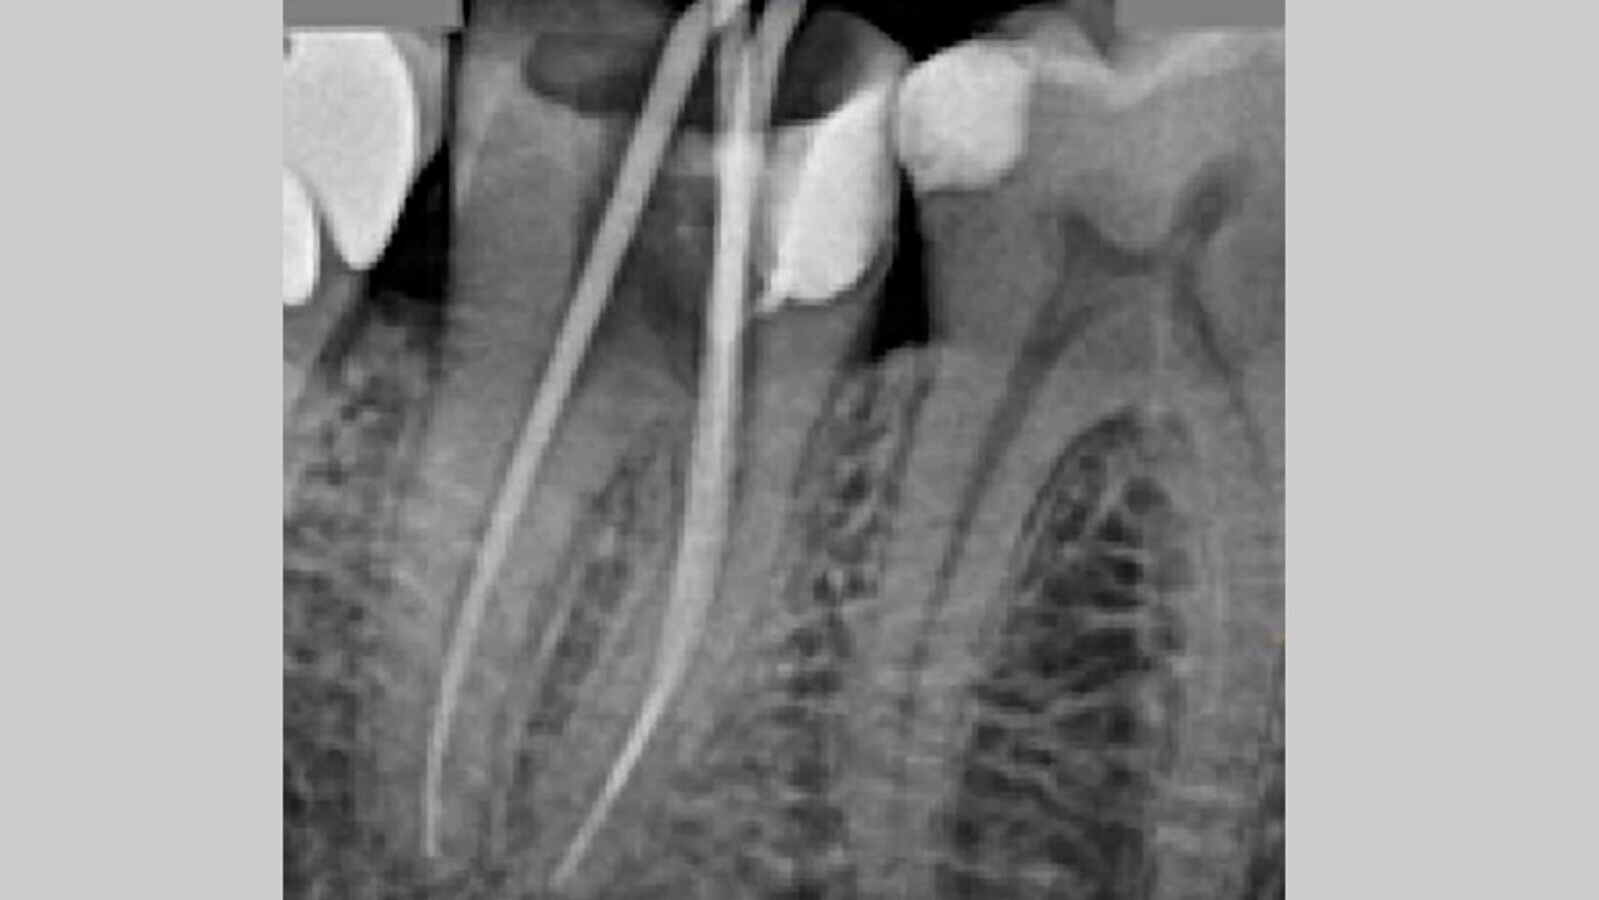

La configuración de los conductos mesiales resulta en la unión en el tercio apical, compartiendo el mismo foramen. Una vez se permeabilizan los conductos con la lima del 10 K- files, se realiza un glide path hasta alcanzar con una lima 15 k file (Denstply) la longitud de trabajo. Es en ese momento se toma una radiografía de comprobación de la longitud de trabajo actual (Fig. 3), y tras confirmar que la longitud es correcta, procedemos a realizar la instrumentación mecánica, en este caso reciprocante con el sistema Reciproc Blue (VDW Dental) que consta de varias limas reciprocantes para la limpieza y conformación de los conductos. Utilizamos este sistema en el motor Endoradar (Woodpecker) el cual viene equipado con localizador electrónico de ápices incorporado. Para la conformación final de los conductos a nivel apical se utiliza el sistema ProFile (Denstply), concretamente la lima ProFile 35.04 en conductos mesiales y la lima 40.04 en el conducto distal. Durante toda la instrumentación irrigamos con NaOCl al 4,25%. Realizamos el protocolo final de activación con activador sónico, tres ciclos: NaOCl 4,25% - EDTA 17% - NaOCl 4,25%. Secamos los conductos con puntas de papel calibradas a los calibres finales de cada conducto (Denstply).

Fig. 3. Radiografía de conductometría. Localización de dos conductos mesiales y un conducto distal.